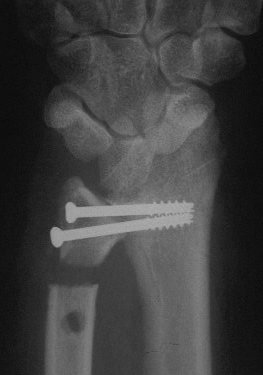

Case 3. Adult bilateral congenital Madelung's deformity with pain and extensor tendinitis, treated with the Sauve Kapandji (Lauenstein) procedure: segmental distal ulnar ostectomy and distal radioulnar joint fusion.

Right side, postop.